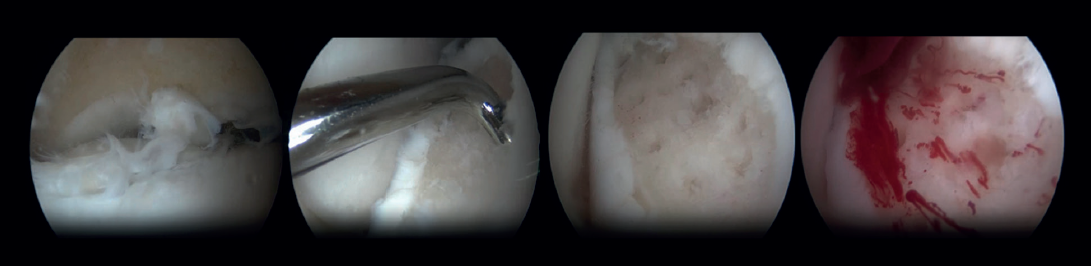

Estimulación de la médula ósea

La estimulación de la médula ósea (EMO) por artroscopia es el tratamiento más frecuentemente utilizado para la lesión osteocondral primaria del astrágalo(22). Es posible utilizar la EMO en lesiones relativamente pequeñas (< 15 mm), no quísticas y no fijables(20,23). La EMO por artroscopia comienza con el desbridamiento y curetaje del cartílago defectuoso y del hueso subcondral(24). Posteriormente, se perfora el hueso esclerótico a la altura de la base del defecto, a menudo con una aguja de Kirschner o un punzón para microfractura(25). Los orificios deben realizarse a una profundidad que provoque la hemorragia del hueso subcondral o la presencia de gotas de grasa(23) (Figura 4). Esta técnica interrumpe los vasos sanguíneos intraóseos, lo que provoca la hemorragia del hueso subcondral y la formación de un coágulo de fibrina. La liberación de células sanguíneas mesenquimales favorece la vascularización, lo que induce la formación de fibrocartílago(26). Cuando se trata de una lesión cartilaginosa aislada (es decir, sin otras lesiones óseas o articulares) con una capa ósea subcondral macroscópicamente intacta, solo puede realizarse un desbridamiento(27).